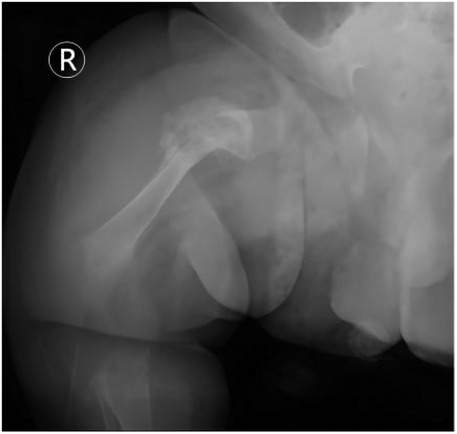

Background: Osteogenesis Imperfecta (OI) poses a unique challenge in pediatric trauma and critical care, where the fragility of bone intersects with life-threatening systemic complications, such as neonatal respiratory failure. The early postnatal period is particularly precarious, demanding a delicate balance between life support and fracture prevention. Case Presentation: A 9-day-old male neonate with prenatally diagnosed COL1A2 (c.1459G>A, p.Gly487Arg) mutation was admitted to our NICU for respiratory distress and pneumonia. He was the progeny of a father with OI, delivered via cesarean section at 34 weeks due to fetal skeletal deformities. Management and Outcomes: A proactive, multidisciplinary team (MDT) protocol was immediately implemented, focusing on non-invasive respiratory support, meticulous handling to prevent iatrogenic injury, and optimized nutrition. This approach successfully resolved his respiratory failure without any new fractures during the NICU stay. However, on the 16th day post-discharge, the infant sustained a spontaneous fracture of the right proximal femur. This was managed conservatively with a Pavlik harness. Follow-up revealed rapid callus formation by day 52 and complete union by day 136, showcasing the characteristic hyperplastic healing pattern of OI. Conclusion: This case underscores that a coordinated MDT approach is vital for stabilizing critically ill neonates with OI. The occurrence of a fracture shortly after discharge highlights the transition to home care as a period of extreme vulnerability. Empowering families with comprehensive education and ensuring continuity of care are as crucial as in-hospital management for improving long-term outcomes in these fragile infants.